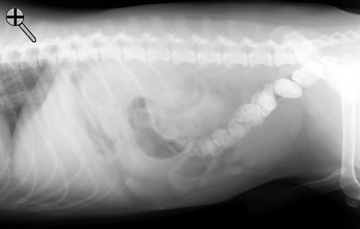

Survey radiographs are taken before administering barium. If you have any questions concerning the technique of an upper GI series, click here to review. Do you notice anything incorrect about the preparation of this patient? YES or NO .